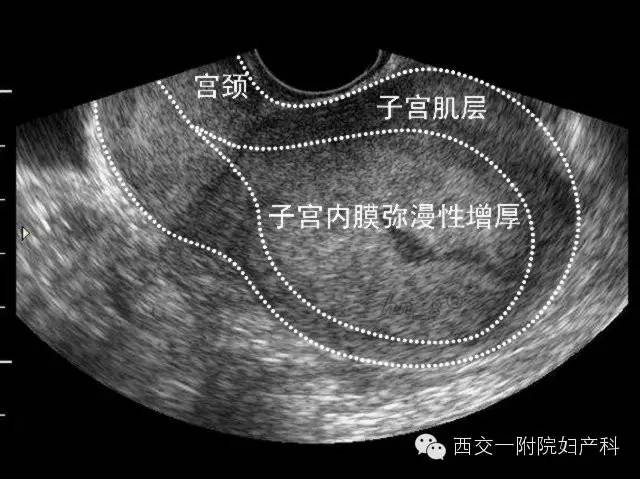

子宫内膜的测量是通过阴道超声所获得的子宫中线矢状切面的最大厚度。它是一个联合子宫内膜前层和后层的宽度所得的双层测量值。

超声检查子宫内膜增厚的描述包括整体增厚、非均匀性增厚、局灶性增厚、积液、血管生成增加和与肌层相关的发现,例如子宫肌层囊肿和黏膜下纤维瘤。

阴道超声不应该用于子宫内膜癌的筛查。绝经后子宫内膜增厚可反映为增生期子宫内膜、子宫内膜囊腺型增生、复杂性增生、非典型增生或子宫内膜癌。

子宫内膜增厚的超声证据也可能反映了结构异常如子宫纵隔、黏膜下子宫肌瘤、息肉或子宫内膜异位症。现在通过识别血流流向的超声技术能够区分息肉和其他异常。

子宫内膜增厚的妇女如果超声有其他阳性的发现,例如血管形成增加,子宫内膜不均匀,颗粒状流体,子宫内膜厚度超过11mm, 应该进行进一步的检查。